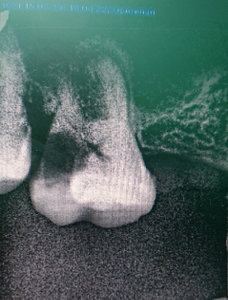

У меня зуб болит. Я его лечила 3 года назад. Мне поставили штифт в декабре 2015, он опять заболел, сделали снимок, оказалось, что он был плохо пролечен. Сняли пломбу, смогли пройти только один канал, во втором канале материал, третий мне врач не смог пройти (инструмент упирался в десну). Тогда еще врач сказал, что этот зуб только удалять, я не согласилась на удаление и мне его просто перекрыли пломбой, теперь опять побаливает.

Как думаете, нужно удалять или его еще можно спасти?

В зубе имеется перфорация, к сожалению, такой зуб спасти и сохранить невозможно.